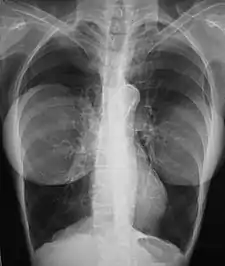

Mammography

The presence of radiologically opaque breast implants (either saline or silicone) might interfere with the radiographic sensitivity of the mammograph, that is, the image might not show any tumor(s) present. In this case, an Eklund view mammogram is required to ascertain either the presence or the absence of a cancerous tumor, wherein the breast implant is manually displaced against the chest wall and the breast is pulled forward, so that the mammograph can visualize a greater volume of the internal tissues; nonetheless, approximately one-third of the breast tissue remains inadequately visualized, resulting in an increased incidence of mammograms with false-negative results.[115][116]

The breast cancer studies Cancer in the Augmented Breast: Diagnosis and Prognosis (1993) and Breast Cancer after Augmentation Mammoplasty (2001) of women with breast implant prostheses reported no significant differences in disease-stage at the time of the diagnosis of cancer; prognoses are similar in both groups of women, with augmented patients at a lower risk for subsequent cancer recurrence or death.[117][118] Conversely, the use of implants for breast reconstruction after breast cancer mastectomy appears to have no negative effect upon the incidence of cancer-related death.[119] That patients with breast implants are more often diagnosed with palpable—but not larger—tumors indicates that equal-sized tumors might be more readily palpated in augmented patients, which might compensate for the impaired mammogram images.[120] The ready palpability of the breast-cancer tumor(s) is consequent to breast tissue thinning by compression, innately in smaller breasts a priori (because they have lesser tissue volumes), and that the implant serves as a radio-opaque base against which a cancerous tumor can be differentiated.[121]

The breast implant has no clinical bearing upon lumpectomy breast-conservation surgery for women who developed breast cancer after the implantation procedure, nor does the breast implant interfere with external beam radiation treatments (XRT); moreover, the post-treatment incidence of breast-tissue fibrosis is common, and thus a consequent increased rate of capsular contracture.[122] There is tentative evidence that women who have had breast augmentation, have worse breast cancer prognosis.[123] The use of implants for breast reconstruction after breast cancer mastectomy appears to have no negative effect upon cancer-related death.[119][124]

There have been multiple reported cases of other adverse effects of mammography of women with breast implants; ruptures resulting from pressure exerted on the breast implant make up a majority of these cases.[125] Compression may also lead to pain or exacerbate already existing pain in the breasts.[125]